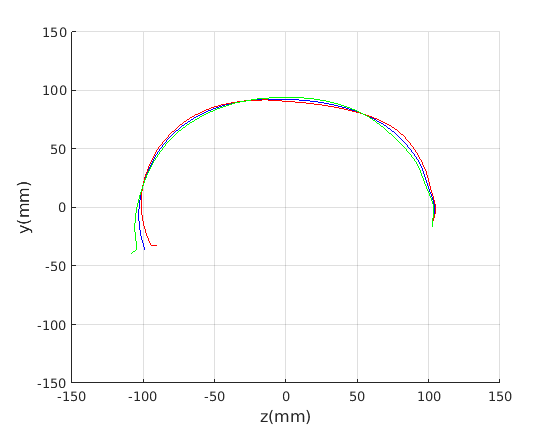

Figure 16 shows examples of the robust ellipse fit for four head profiles. The centre of the ellipse is used in a pose normalisation procedure where the ellipse centre is used as the origin of the profile and the angle from the ellipse centre to the nasion is fixed at -10 degrees. We call this Ellipse Centre - Nasion (ECN) pose normalisation and later compare this to GPA. The major and minor axes of the extracted ellipses are plotted as red and green lines respectively in Fig. 16.

|

Figure 17 shows all 100 profiles overlaid with the same alignment scheme. The median value of major ellipse axis and the ellipse centre-nasion angle differ by 3.6 degrees, so that when the nasion angle is fixed at -10 degrees, the median ellipse angle is -6.4 degrees (cf. -7.4 degrees with manual landmarking of the nasion). We noted regularity in the orientation of the fitted ellipse as is indicated by the clustering of the major (red) and minor (green) axes in Fig. 17 and the histogram of ellipse orientations in Fig. 18. For most people, the major axis of the ellipse is closely aligned with the y-axis (upright), and titled slightly forwards. A minority of heads (9%) in the training sample have their major ellipse axes closer to the vertical (these relatively tall and short heads are known as brachycephalic.) Ellipse axis clustering (relative to the fixed ellipse centre-nasion line) does not appear to be sharply defined. This is because many crania are close to circular in cross-section, making the orientation of these angles sensitive to small changes in shape from one person to the next. Note also the variation at the back of the head due to a variety of hair styles, some of which protrude from under the cap. We limit the region over which we model the cranial shape in order to crop this unwanted data out.